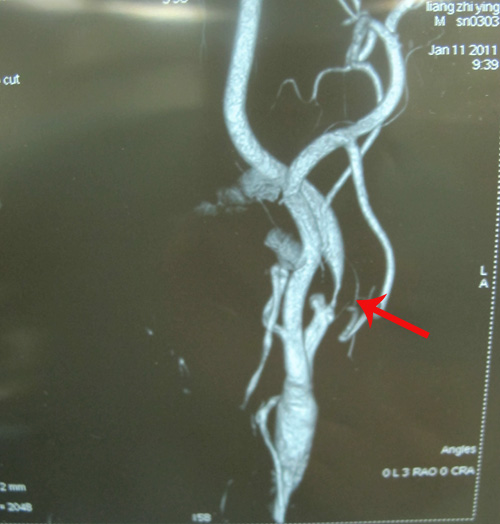

全脑血管造影:1.左侧颈内动脉狭窄(约90%),合并溃疡性斑块。2、右侧颈外动脉狭窄(约40%),颈内动脉起始段狭窄(约50%),海绵窦段动脉硬化,眼动脉起始段狭窄(约70%),大脑前动脉A1段缺如。

颈部血管超声:左侧颈内动脉狭窄;左侧颈内动脉、右侧颈总动脉、头臂干粥样斑块形成;右侧椎动脉内径细,血流量低;左侧颈总动脉、左侧椎动脉未见异常。

左侧颈动脉粥样硬化斑块形成伴狭窄(约90%)

右侧颈动脉粥样硬化斑块形成伴狭窄(约50%)